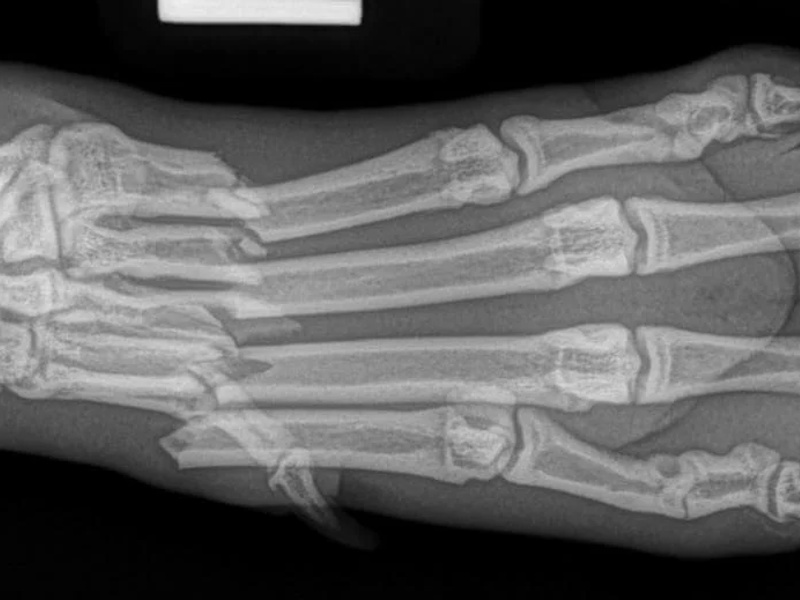

Fore Limb (Humerus, Radius/Ulnar, Metacarpus)